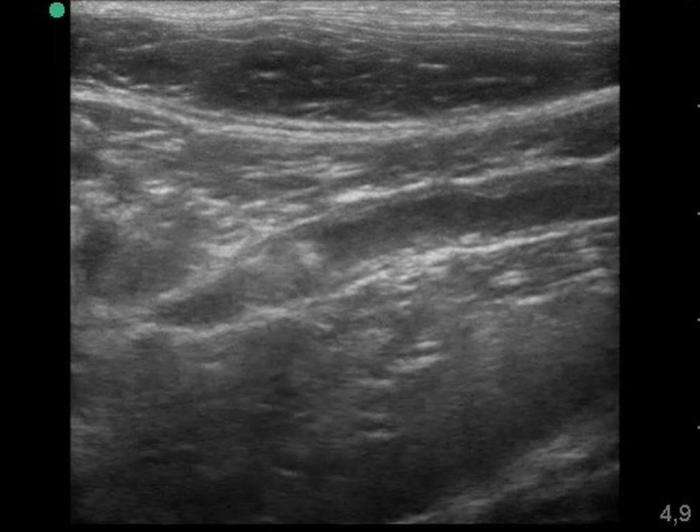

El estudio ultrasonográfico abdominal se realizó con un ecógrafo marca Mindray® modelo Z60Vet®, con transductor de 12 MHz. El estudio reveló los siguientes hallazgos (Figura 2-4):

- Hiperecogenicidad difusa e irregularidad de contornos en la rama derecha del páncreas.

- Dilatación del conducto pancreático derecho, alcanzando 0.49 cm de diámetro.

- Imagen hiperecogénica intraductal con sombra acústica posterior y artefacto de centelleo en Doppler color, compatible con litiasis.